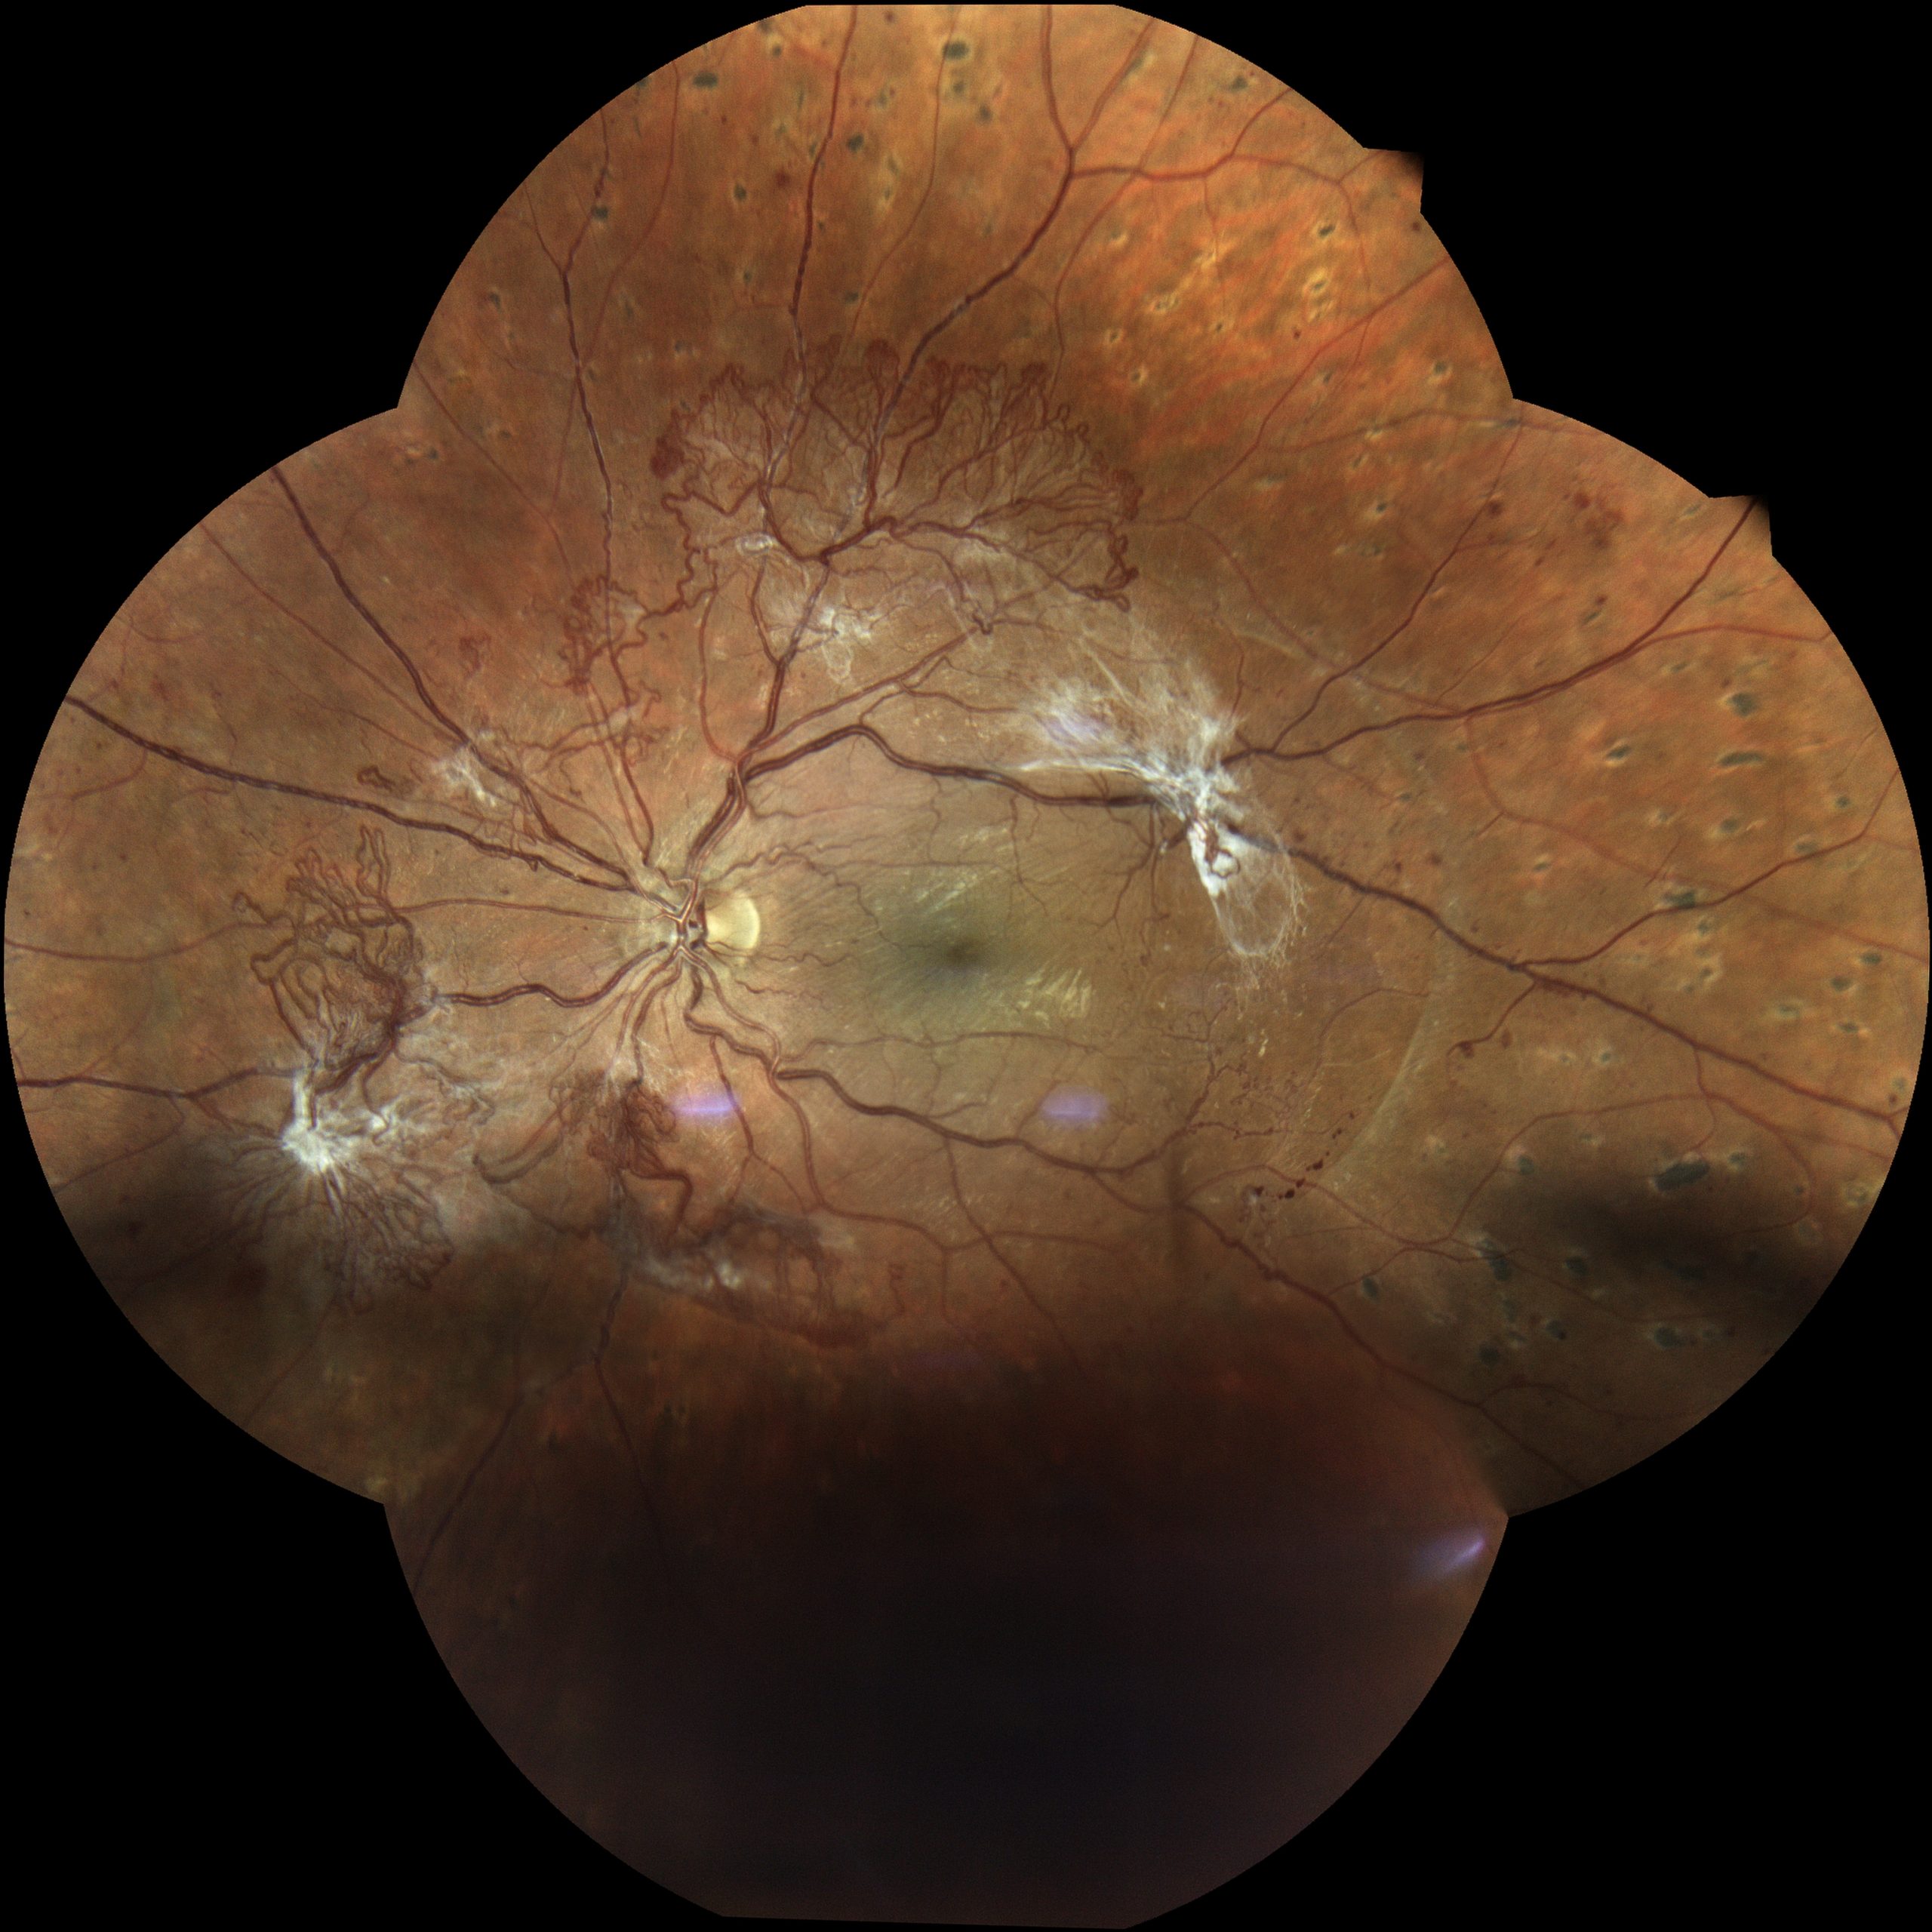

Jeder Augenarzt und jede Augenärztin kennt solche Beispiele aus der Praxis: Ein Patient kommt mit einem Bindehauttumor in die Praxis. Das kann ein harmloser Nävus sein – eine gutartige Fehlbildung wie es auch ein Muttermal ist (Abbildungen 1 und 2). Es kann aber auch ein bösartiger Tumor sein. Deshalb gilt es genau hinzuschauen und den Verlauf zu beobachten: Verändert er sich von einer Untersuchung zur nächsten? Dies lässt sich jedoch ohne eine Fotografie nicht dokumentieren. Ein anderes Beispiel ist das Netzhautscreening bei Menschen mit Diabetes: Sie sollen regelmäßig augenärztlich untersucht werden, um bei Schäden an der Netzhaut rechtzeitig reagieren zu können. Auch hier ist es unerlässlich, bei jeder Untersuchung Fotos der Netzhaut anzufertigen, um Veränderungen im Detail nachvollziehen zu können (Abbildungen 3 und 4).